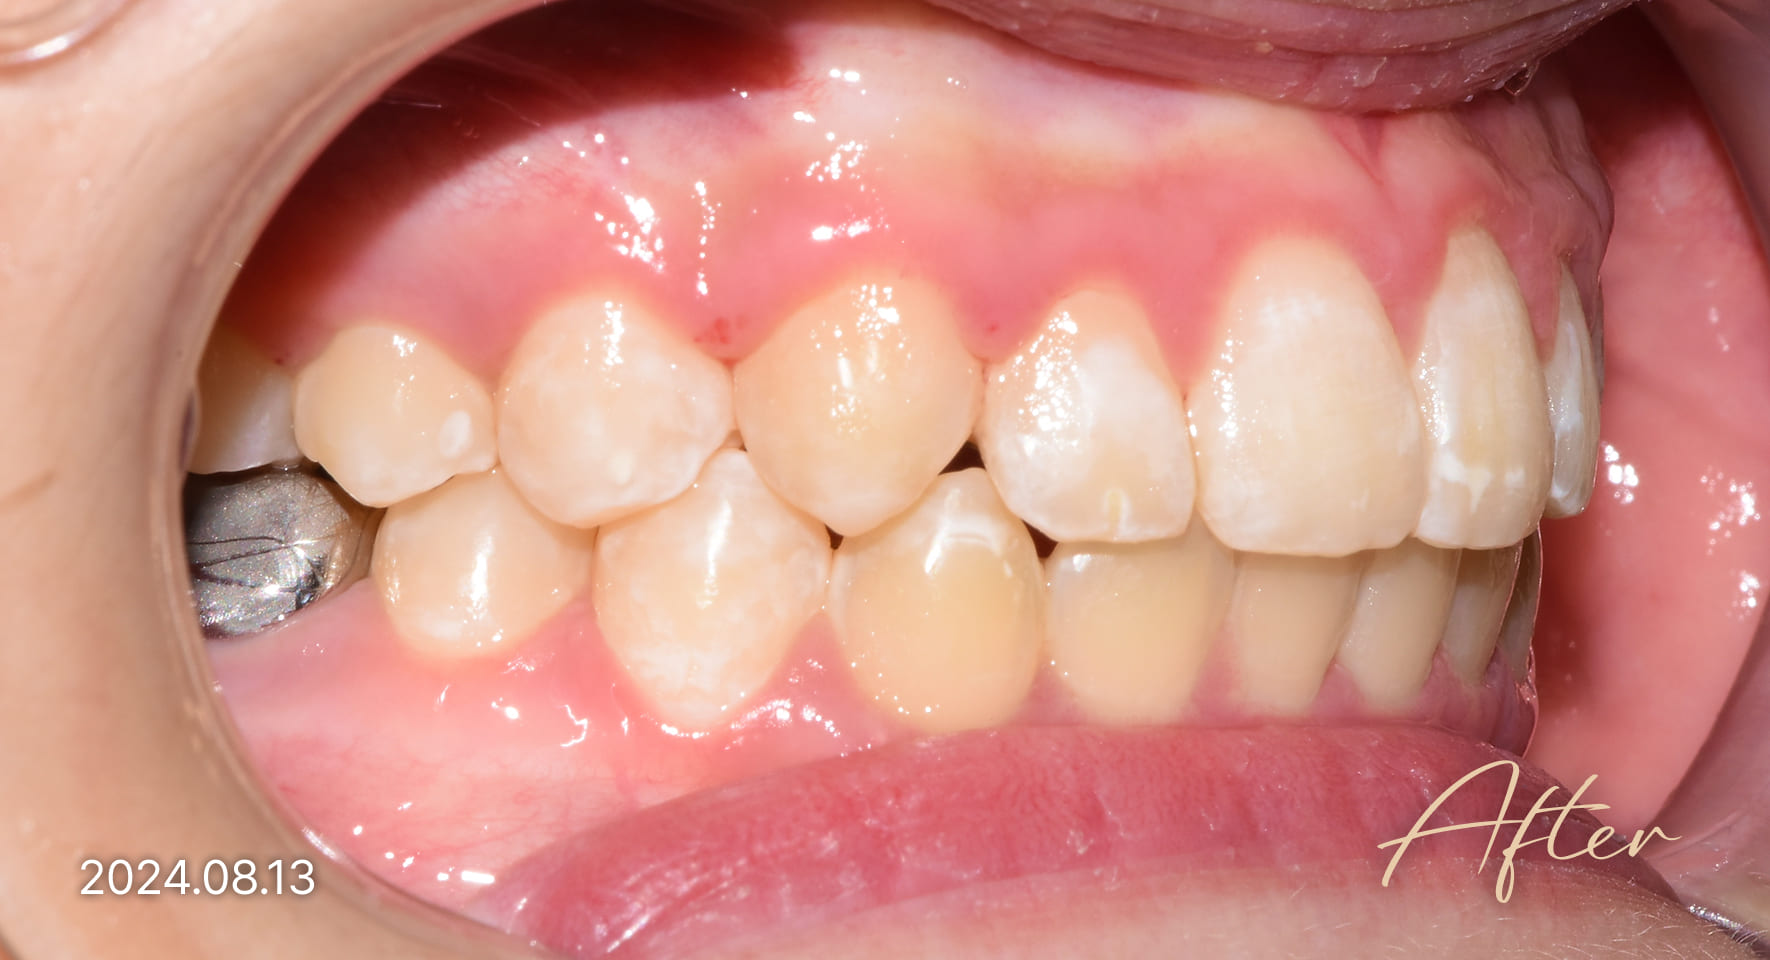

성장기 교정 치료사례

본 사진은 진심을담은치과교정과 치과의원에서

치료한 환자의 동일 인물 전·후 사진입니다.

개인의 구강 상태 및 관리 방법에 따라 통증 및 잇몸 염증,

턱관절 불편감 등의 부작용이 발생할 수 있습니다.

치료 전 치료 후